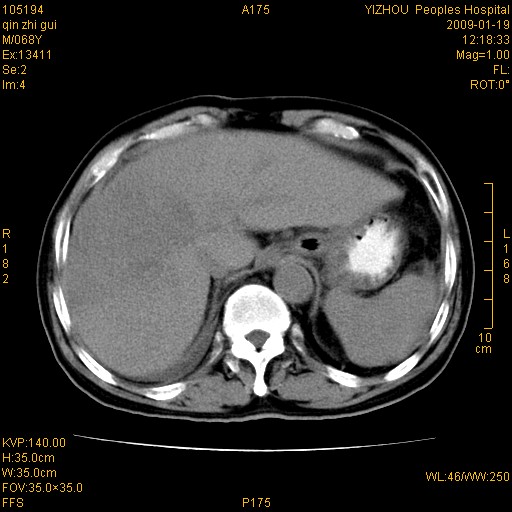

以下是引用随光逐影在2009-1-21 16:11:00的发言:[br]1)考虑肝右叶肝癌并肝静脉及门静脉瘤栓形成。2)肝硬化,少量腹水。3)胆囊炎。4)右侧少量胸腔积液。

病灶外缘凹凸不平,平扫低密度,增强动脉期有强化,门脉早显,静脉期及延期呈延迟强化,结合病史考虑右肝前叶巨块型肝癌可能性大,强化表现不除外胆管细胞癌